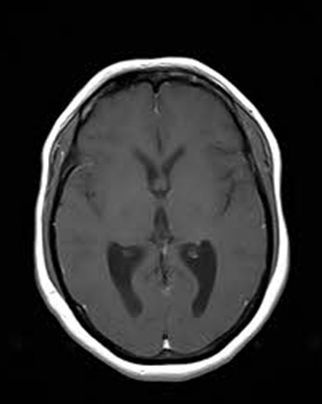

An Occipital Headache as the First Presentation of Multiple Third, Fourth, and Lateral Ventricular Cavernous Malformations: A Case Report and Review of Literature

Background: Cavernous hemangiomas are common benign vascular malformations. Their existence in the intraventricular region is very rare. Case Reports: A 43-year old woman with an occipital headache was admitted to the emergency ward. Brain computed tomography scan showed mild hydrocephalus and multiple intraventricular isodense lesions. Imaging findings, especially of Gradient Resonance Echo imaging, were in favor of multiple intraventricular cavernous malformations. Conclusion: This is a rare presentation of multiple cavernous malformation as occipital headache without needing surgical intervention in this phase. Coexistence of periventricular plaques like Radiologically isolated syndrome of Multiple sclerosis is another unique aspect in this report. [GMJ.2017;6(1):61-65]